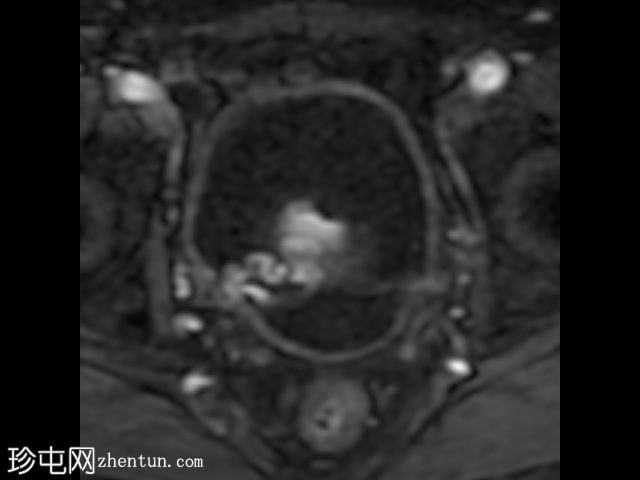

轴位

T2加权像

在T1和T2加权像上,于膀胱底部及右下外侧面偶然发现一处呈蛇形缠绕状的低信号区。动态序列中可见快速对比增强,提示所有影像学表现均源于血管,信号缺失与动静脉畸形有关,该畸形至少由膀胱下动脉供血,并由同侧局部扩张的静脉回流。